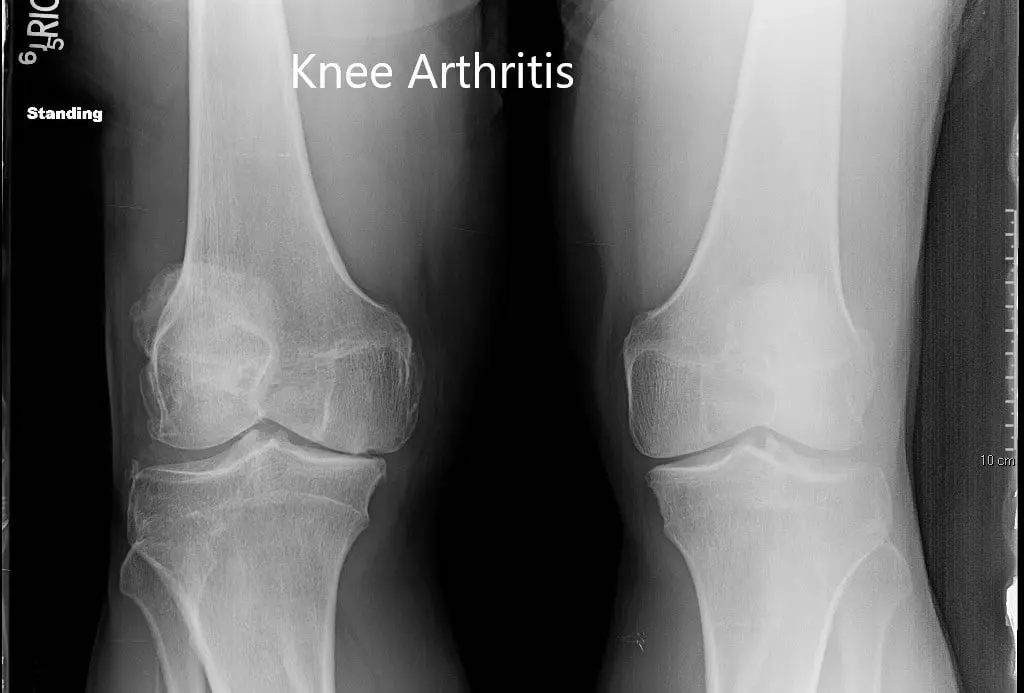

Imaging studies revealed severe tricompartmental osteoarthritis of the right knee. Considering the lifestyle limiting knee pain, the patient was advised right total knee replacement. All the risks, benefits and alternatives were discussed in detail with the patient. The patient agreed to go ahead with the procedure.

Preoperative X-ray of both the knees in anteroposterior view.